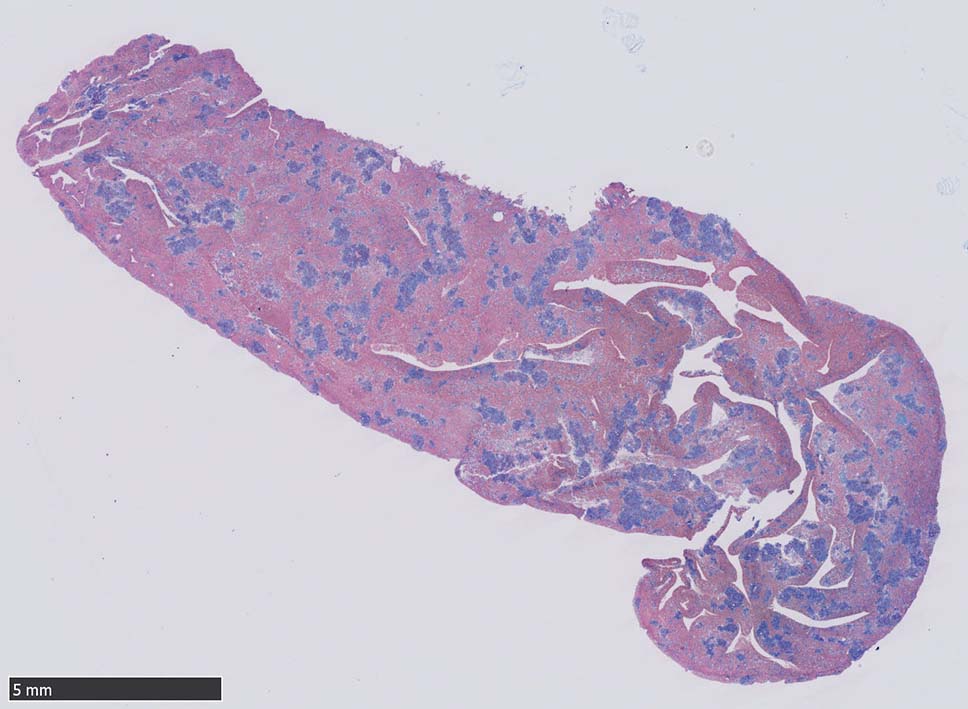

肝臓  サムネイルのクリックで大きな画像が見られます.

肝針生検組織; 類洞に細胞浸潤が認められ, 非浸潤部との境界がぼんやりと認められる. 類洞と異なり, グリソン鞘は腫瘍細胞の浸潤が乏しいか, ほとんど認められない.

類洞内に浸潤増殖するリンパ腫細胞: 類円形・長円, 瓜状の核をもつ,細胞質の乏しい細胞(サムネイル画像のクリックで大きな画像が見られます)